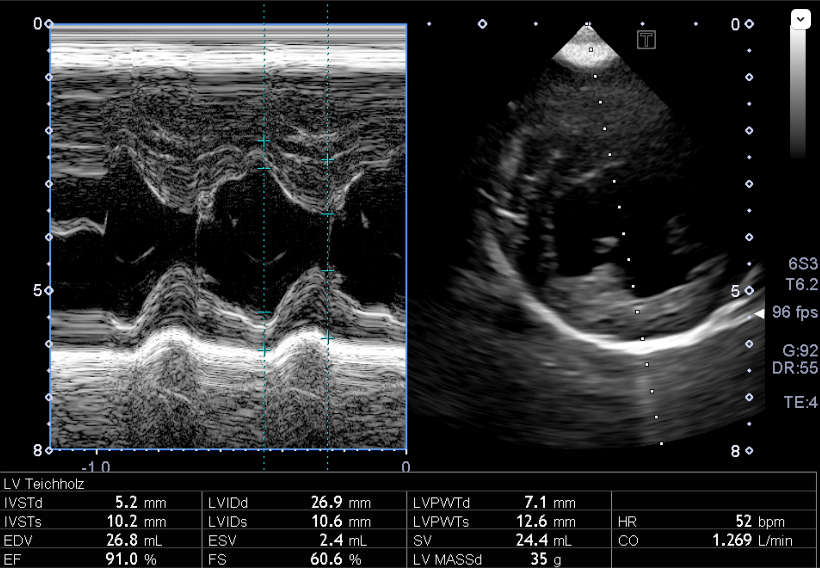

心臓エコー内服開始6年目